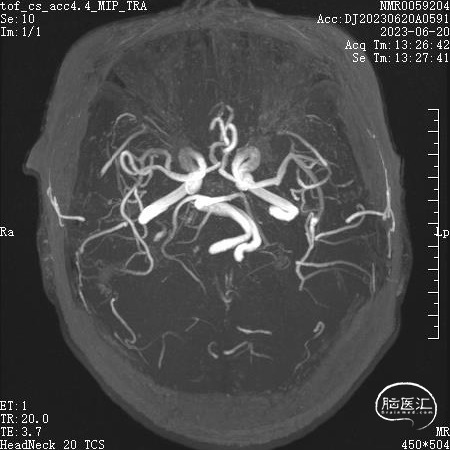

MRI:可见左侧椎动脉和小脑前下动脉压迫面神经REZ区

手术过程:常规乙状窦后入路准备,侧卧位,乳突后发迹内直切口,约6cm,暴露星点后于其前下方颅骨钻孔,铣刀游离骨瓣,磨钻扩大骨窗到达乙状窦后缘,骨窗直径约3cm,硬膜外止血满意(确保剪开硬脑膜后术区为无血状态)后T形切开硬脑膜并悬吊,窄脑压板牵开小脑后释放脑脊液脑压下降满意后于后组颅神经处剪开蛛网膜进一步释放脑脊液,分离小脑绒球与后组颅神经粘连,在面听神经和后组颅神经间可见粗大椎动脉走行面神经REZ区,抬起椎动脉后见小脑前下动脉紧贴于脑干及面神经,将椎动脉及小脑前下动脉分别给予Teflon垫棉隔离,此时电生理提示LSR仍部分存在,调整头位及显微镜角度后见内听动脉沿面神经腹侧走行,小心分离,无明显穿支血管,给予垫棉隔离后电生理提示侧方扩散波消失。术区反复温生理盐水冲洗,止血满意后水密缝合硬脑膜,必要时用肌肉/筋膜修补缝合,骨瓣用连接片固定复位后逐层关颅,避免各层间死腔。患者清醒后未见面部 抽搐。

本例面肌痉挛病人由椎动脉+小脑前下动脉+內听动脉三级血管共同压迫所导致,临床罕见,尤其內听动脉参与面肌痉挛相当少见,此外,椎动脉压迫引起的面肌痉挛,约占23%,可以一侧椎动脉压迫、双侧椎动脉压迫或者单纯对侧椎动脉压迫,因椎动脉血管壁硬化,或者手术操作空间狭窄,使手术复杂程度增加,术后有效率也随之降低,通过不断实践,我们认为通过对椎动脉架桥、悬吊等可以使椎动脉的微血管减压取得良好的减压效果,并且我们有电生理实时监测LSR,根据实时监测的变化及时调整手术策略,把电生理监测LSR消失作为手术终点,确保患者手术取得良好手术效果。